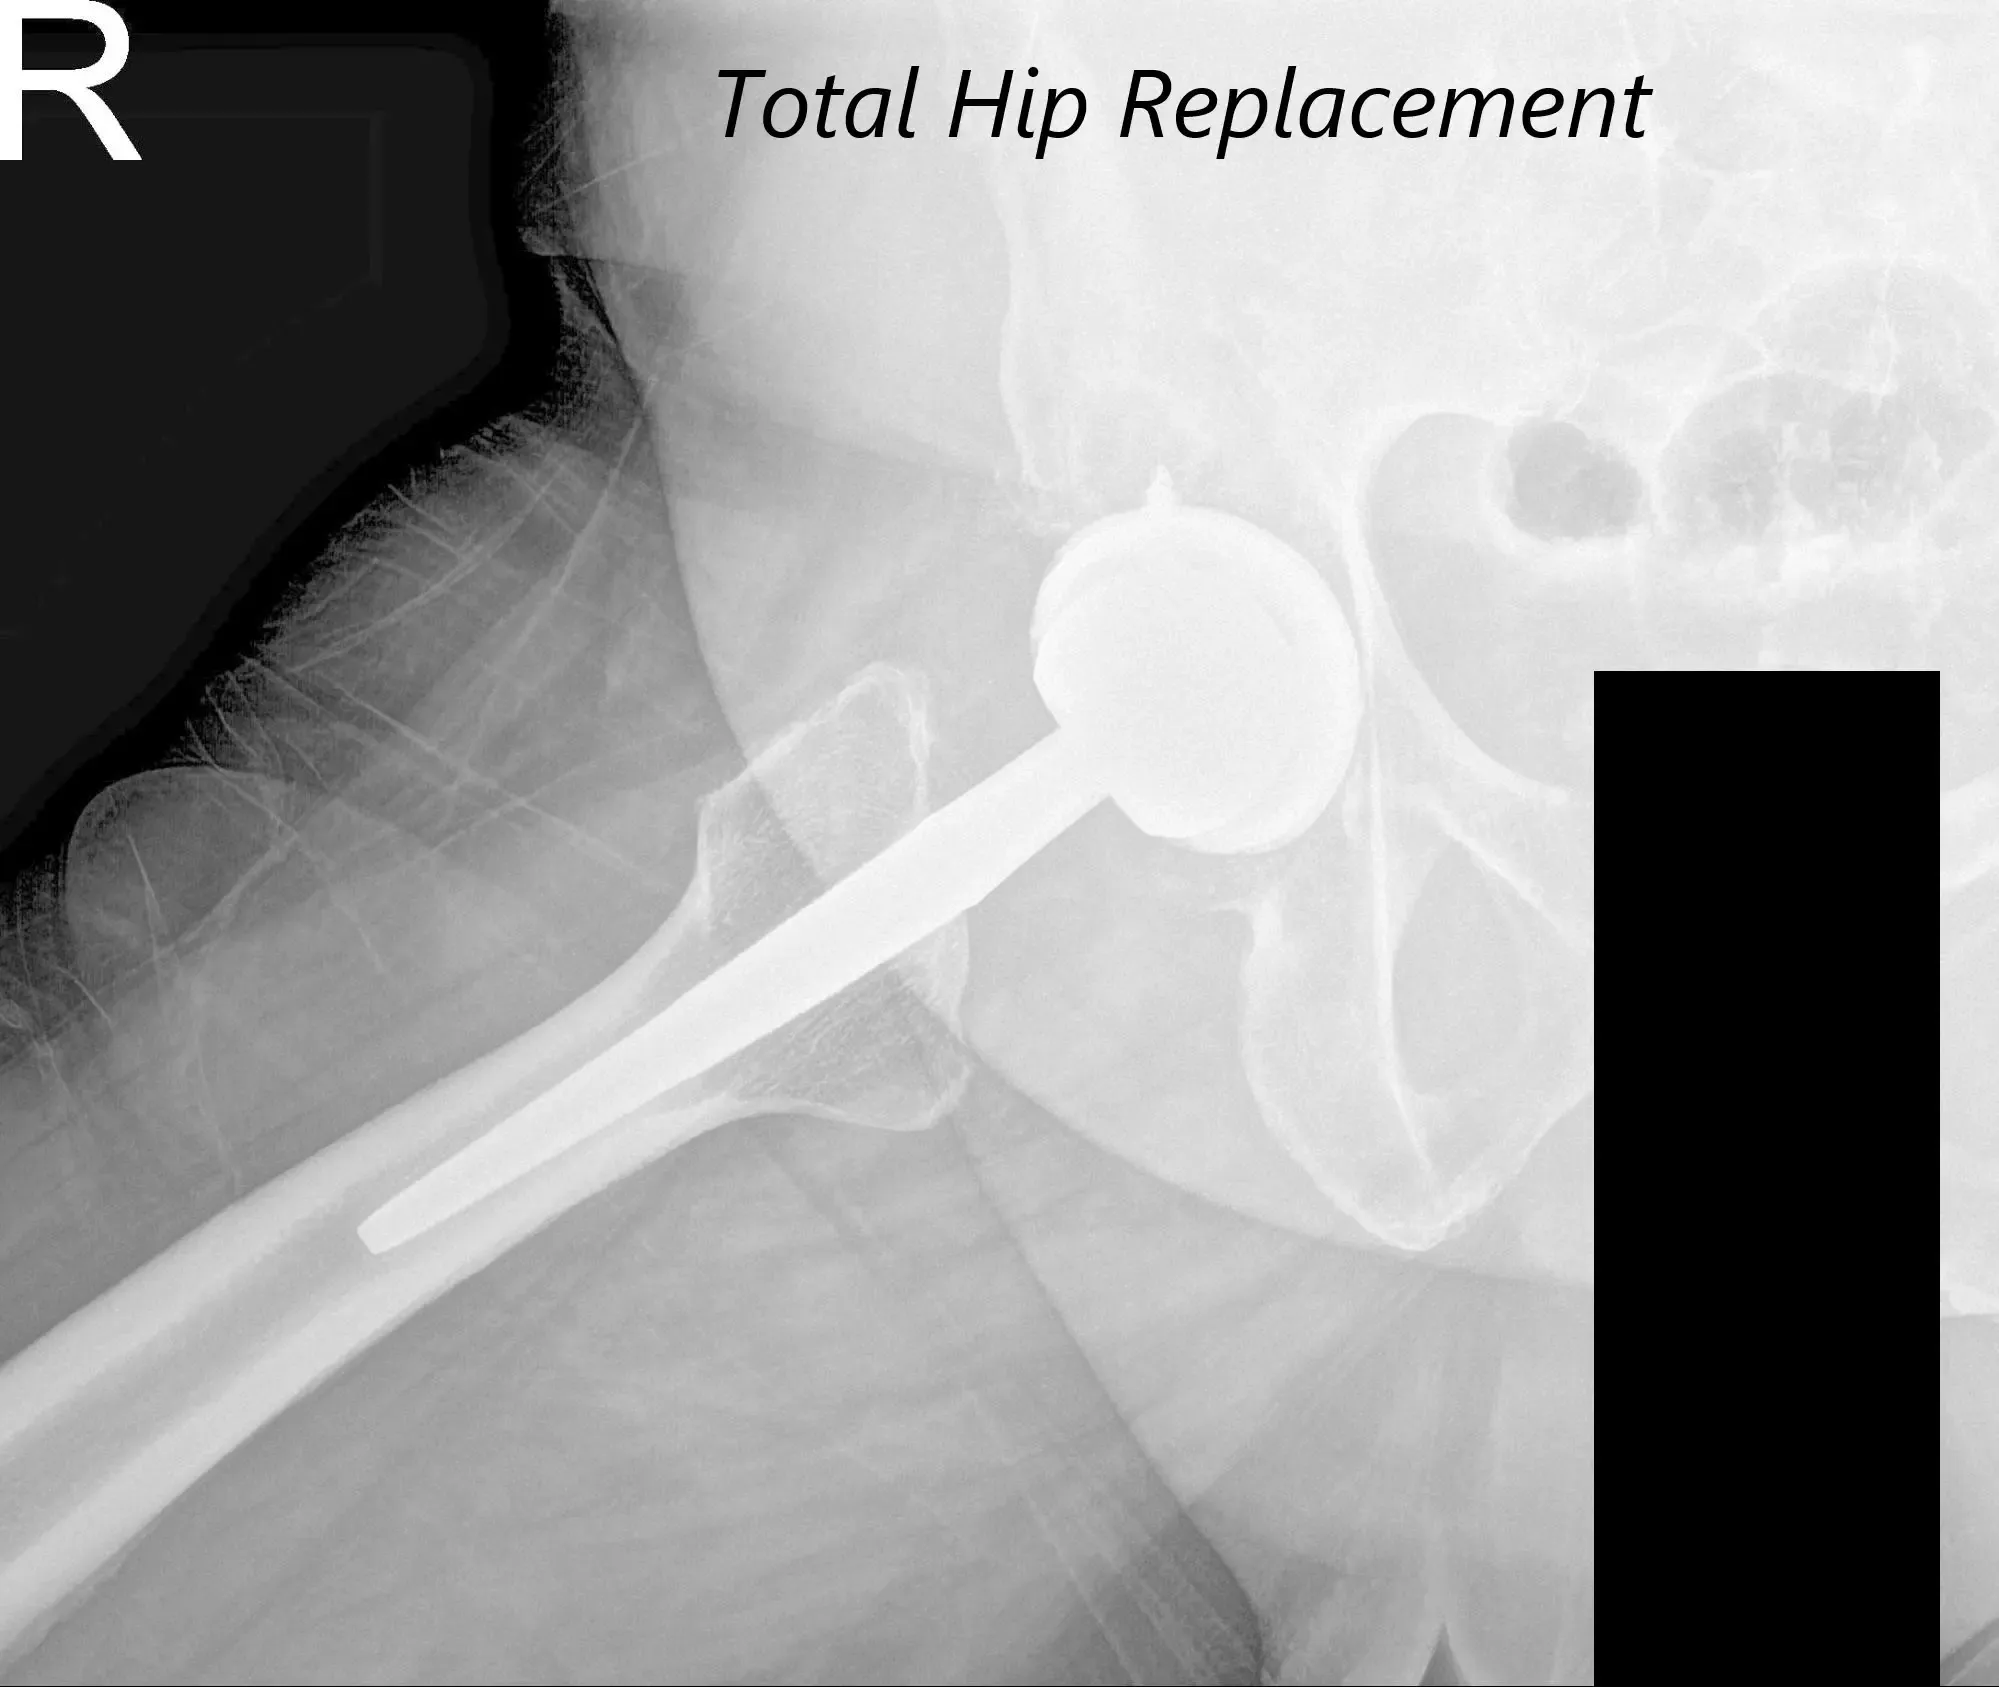

AP view of the Pelvis X ray showing both hip joints with frog leg lateral views of the right and left hip joints suggesting severe bilateral osteoarthritis of the hip joints.

There was bilateral anterior Hip joint line tenderness. The bilateral digital Bryant triangle was comparable suggesting no suprapelvic shortening or lengthening. Imaging studies revealed severe bilateral hip arthritis.